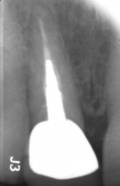

Ein Implantat trägt nicht nur zur Wiederherstellung von Kaufunktion und Ästhetik bei, sondern schützt auch den Kieferknochen vor Abbauprozessen, die nach Zahnverlust auftreten können. Voraussetzung für den langfristigen Erfolg ist eine sorgfältige Planung unter Berücksichtigung von Knochenangebot, Weichgewebe, Funktion und individueller Belastung.